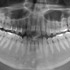

Nacholgend ein paar phänomenale Bilder & Werte,

die nicht nur einem Fachmann die Sprache verschlagen:

Aufnahmeparameter: Ceph LA; 82 kV; 10 mA; 8.0 s; 0.8 mm CU + 6.0 mm AL

gemessene Dosis: 2.99 µGy